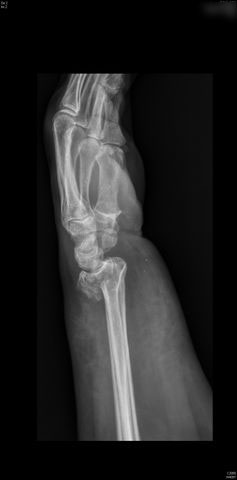

Fractura de húmero, intensa desviación de fragmentos